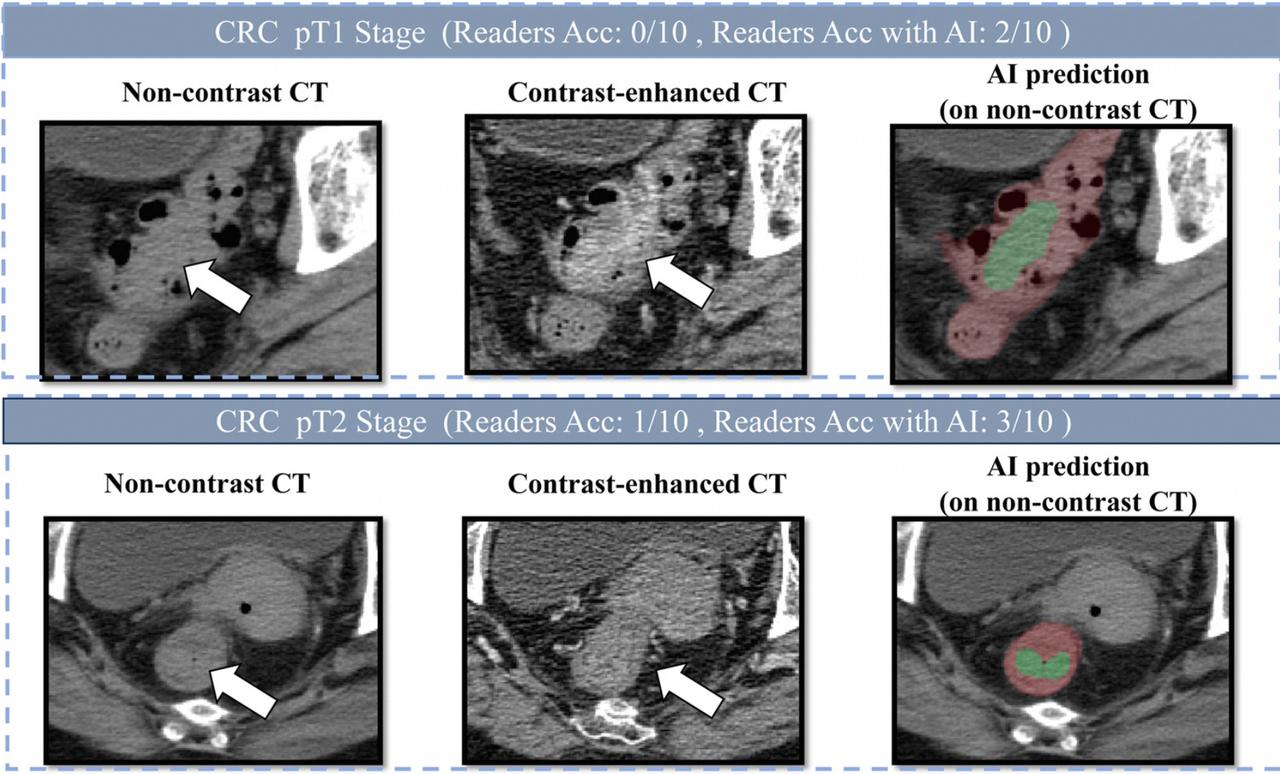

阿里达摩院联合广东省人民医院等机构研发出来了肠癌早筛模型DAMO COCA,借助这个模型,患者只需要用自己平时做的平扫CT影像就能进行肠癌筛查,相关论文还登上了国际顶刊《肿瘤学年鉴》。

更牛的是,此前DAMO COCA从2.7万人的平扫CT影像中精准识别5例漏诊肠癌,敏感性、特异性分别达到86.6%和99.8%,误诊的概率极低。